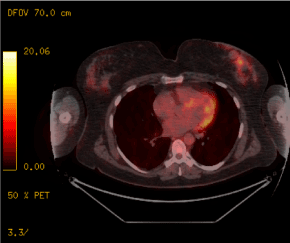

Two years after the end of radiotherapy, as part of its surveillance, a PET scanner showed an increase in the size of intra-mammary lesions compared to the left breast scar without any argument for secondary localization. Until now, microbiopsies found only postoperative changes with a significant inflammatory reaction of the chronic xanthogranulomatous type, presumably indicative of an old hematoma (Figure 1-3). Level II oncoplastic lumpectomy was performed (Figure 4). Histopathological analysis revealed an intra-mammary metastasis of well-differentiated squamous cell carcinoma of 0.5 cm and an abscess being organized (Figure 5). Also noted was the presence of a low grade in situ ductal carcinoma microfocus located 0.5 mm from the lower limit and a microfocus of lobular carcinoma in situ located 0.5 mm from the deep limit. There was a theoretical indication for left breast radiotherapy but given the size of the DCIS and its grade, as well as the history of irradiation nearby, it was decided not to perform adjuvant therapy. Six months later, the patient did not show signs of relapse.

Figure 3. PET scan. Appearance of a left lobular retro-nipple-shaped nodular image with heterogeneous peripheral hypermetabolism